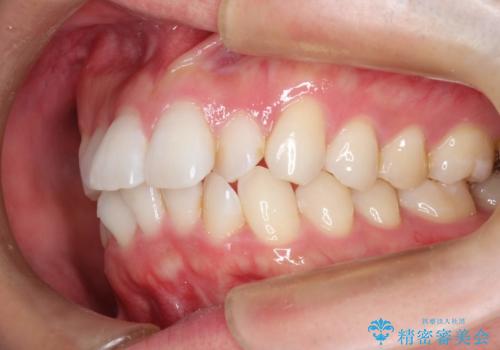

フルリンガル矯正 非抜歯でガタつきを整える

- フルリンガルワイヤーによる非抜歯治療を計画しました。